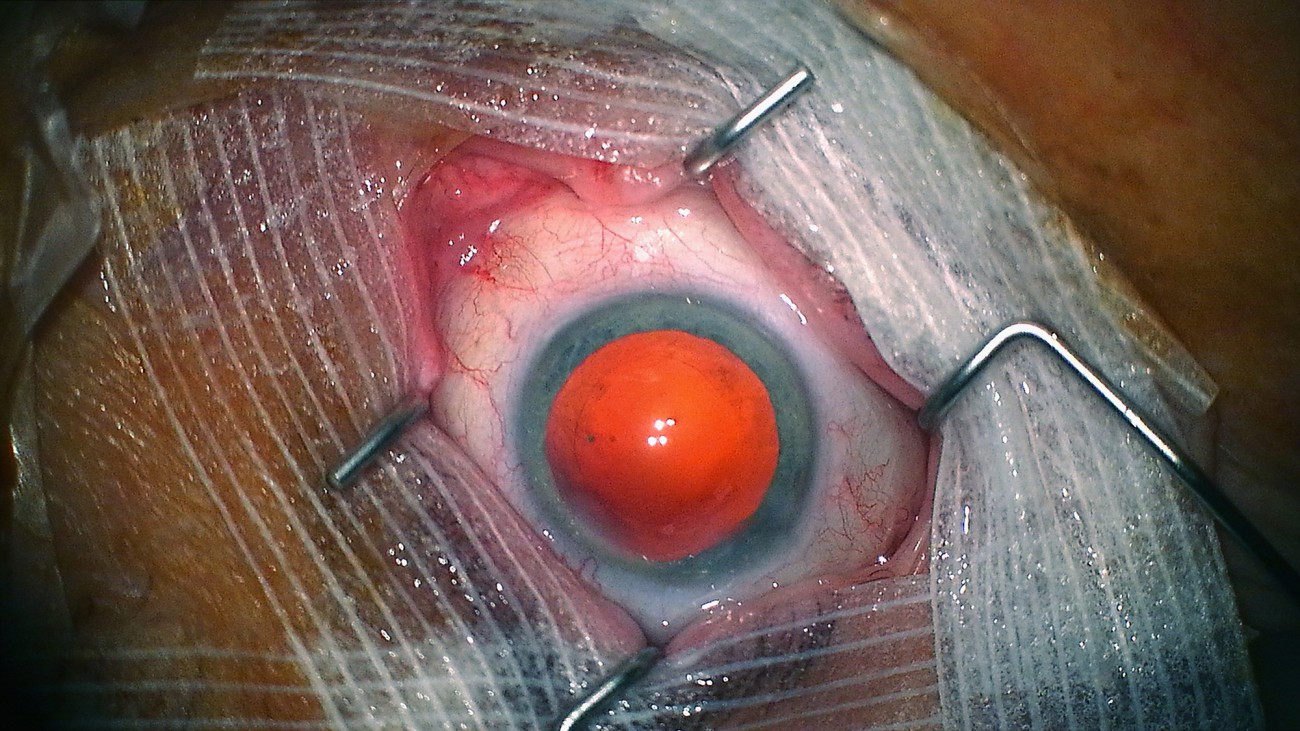

Reprenant le titre d’un traité d’anatomie du XVIe siècle, «De Humani Corporis Fabrica» s’intéresse à ce qui se passe non pas à l’intérieur de l’hôpital mais à l’intérieur des patients. Aux liens qui unissent le corps médical aux corps défaillants, fracassés, au bord de l’extinction. Il y a cinq siècles l’anatomiste André Vésale ouvrait pour la première fois le corps au regard de la science. «De Humani Corporis Fabrica» ouvre aujourd’hui le corps au cinéma. On y découvre que la chair humaine est un paysage inouï qui n'existe que grâce aux regards et aux attentions des autres. Les hôpitaux, lieux de soin et de souffrance, sont des laboratoires qui relient tous les corps du monde…